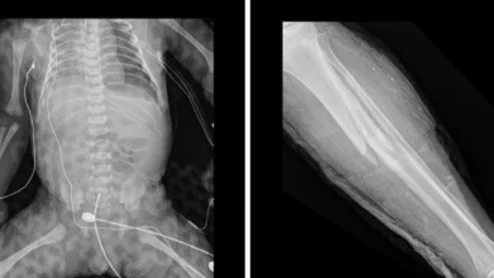

Radiology providers from Israel share how their hospital handled the mass casualties caused by the October 2023 terror attacks.

Soroka University Medical Center served as the primary evacuation destination after the attack, accepting nearly 700 injured patients, most of whom needed medical imaging.